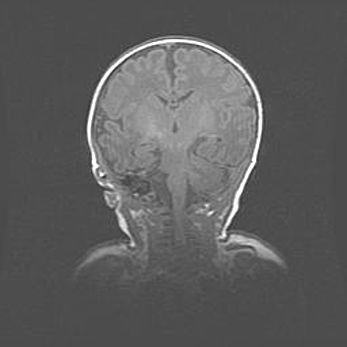

Открытая гидроцефалия.

Возраст: 6 месяцев 15 дней

Вес: 6200 г

Пол: женский

Окружность головы: 41 см

Срок гестации: 38 недель

Гидроцефалия головного мозга у новорожденных – это скопление избыточного количества цереброспинальной жидкости в головном мозге. Ее избыточное скопление в мозге приводит к патологическому расширению желудочков мозга (четырех полостей, расположенных в глубине белого вещества мозга, заполненных цереброспинальной жидкостью и связанных узкими проходами).

Открытый тип гидроцефалии (сообщающаяся) наблюдается тогда, когда нарушен механизм всасывания ликвора в системный кровоток. При этом типе причиной заболевания чаще всего является перенесенные ранее инфекции (например: менингит),  либо же наличие крови в субарахноидальном пространстве.